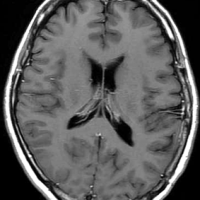

典型的な髄膜腫

この髄膜腫は中程度の大きさのものです。円蓋部髄膜種という最も多い最も手術の簡単なタイプです。麻痺や失語症やてんかんなどの症状はありません。とても美しくて若い女性の髄膜腫でしたが,子供に遺伝はしませんし,癌などと違ってタバコなどこれといった原因がなくて発生するものです。

MRIでの髄膜腫の見え方は撮影の仕方によっていろいろです。左からT1強調画像,T2強調画像,フレア画像といいます。腫瘍の横に小さく白い領域がありますが,これは脳の腫れた部分で脳浮腫といいます。髄膜腫があると周囲に脳浮腫が生じることがあります。

最も見やすいのが,ガドリニウム造影剤を注射して撮影するものです。一般的に髄膜腫は造影剤で白く映し出されます。この腫瘍は左脳側にあります。MRIの軸面という輪切りの写真では左右が逆になりますから注意してください。脳を下から見た図になっています。MRIはいろいろな方向から腫瘍を見ることができますが,右は冠状断という正面から見た図です。よく見ると腫瘍の上と下のはじっこに線状に糸を引いたように造影される部分があります。これをテールサイン(しっぽのサイン)といいます。腫瘍が硬膜に沿って延びている可能性があることを示しています。

手術後のMRIです。腫瘍は全部取れていて後遺症もありません。圧迫されて変形していた脳はきれいに元に戻っていますし脳浮腫も消えました。一般的に若い人の脳ほどきれいに元に戻ります。注意しなければならないのは,少しでも取り残した場合には,何年か後に10%-20%くらいで再発があることです。もちろん完全に取れた時の再発はほとんどありません。